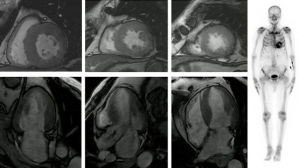

Ce patient de 86 ans est hospitalisé pour des lésions dermatologiques aspécifiques. Il présente plusieurs facteurs de risque cardiovasculaire : un tabagisme ancien, un diabète de type 2, de l’hypertension, une dyslipidémie et un surpoids. Il est également atteint d’une surdité non appareillée et d’une maladie aortique.